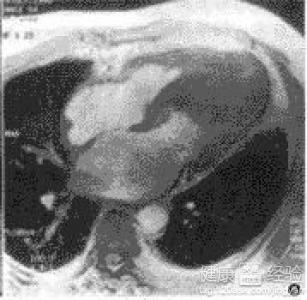

摘要:關(guān)于擴張性心肌病的最新治療,小巷深處的隱藏寶藏正逐漸為人們所發(fā)現(xiàn)。通過先進的醫(yī)療技術(shù)和方法,擴張性心肌病的治療取得了新的進展。這些治療方法旨在改善心臟功能,提高患者生活質(zhì)量。小巷深處的醫(yī)療機構(gòu)或?qū)<铱赡茈[藏著寶貴的治療經(jīng)驗和方法,為尋求最佳治療方案的病患帶來希望。更多詳細信息需要進一步探索和研究。

擴張性心肌病是一種嚴重的心臟疾病,但“心之港灣”為你帶來希望,這里的專家團隊一直在深入研究擴張性心肌病的最新治療方法,并深知每位患者都渴望得到最佳的治療和關(guān)懷,他們努力不懈,為患者帶來生機和新生。